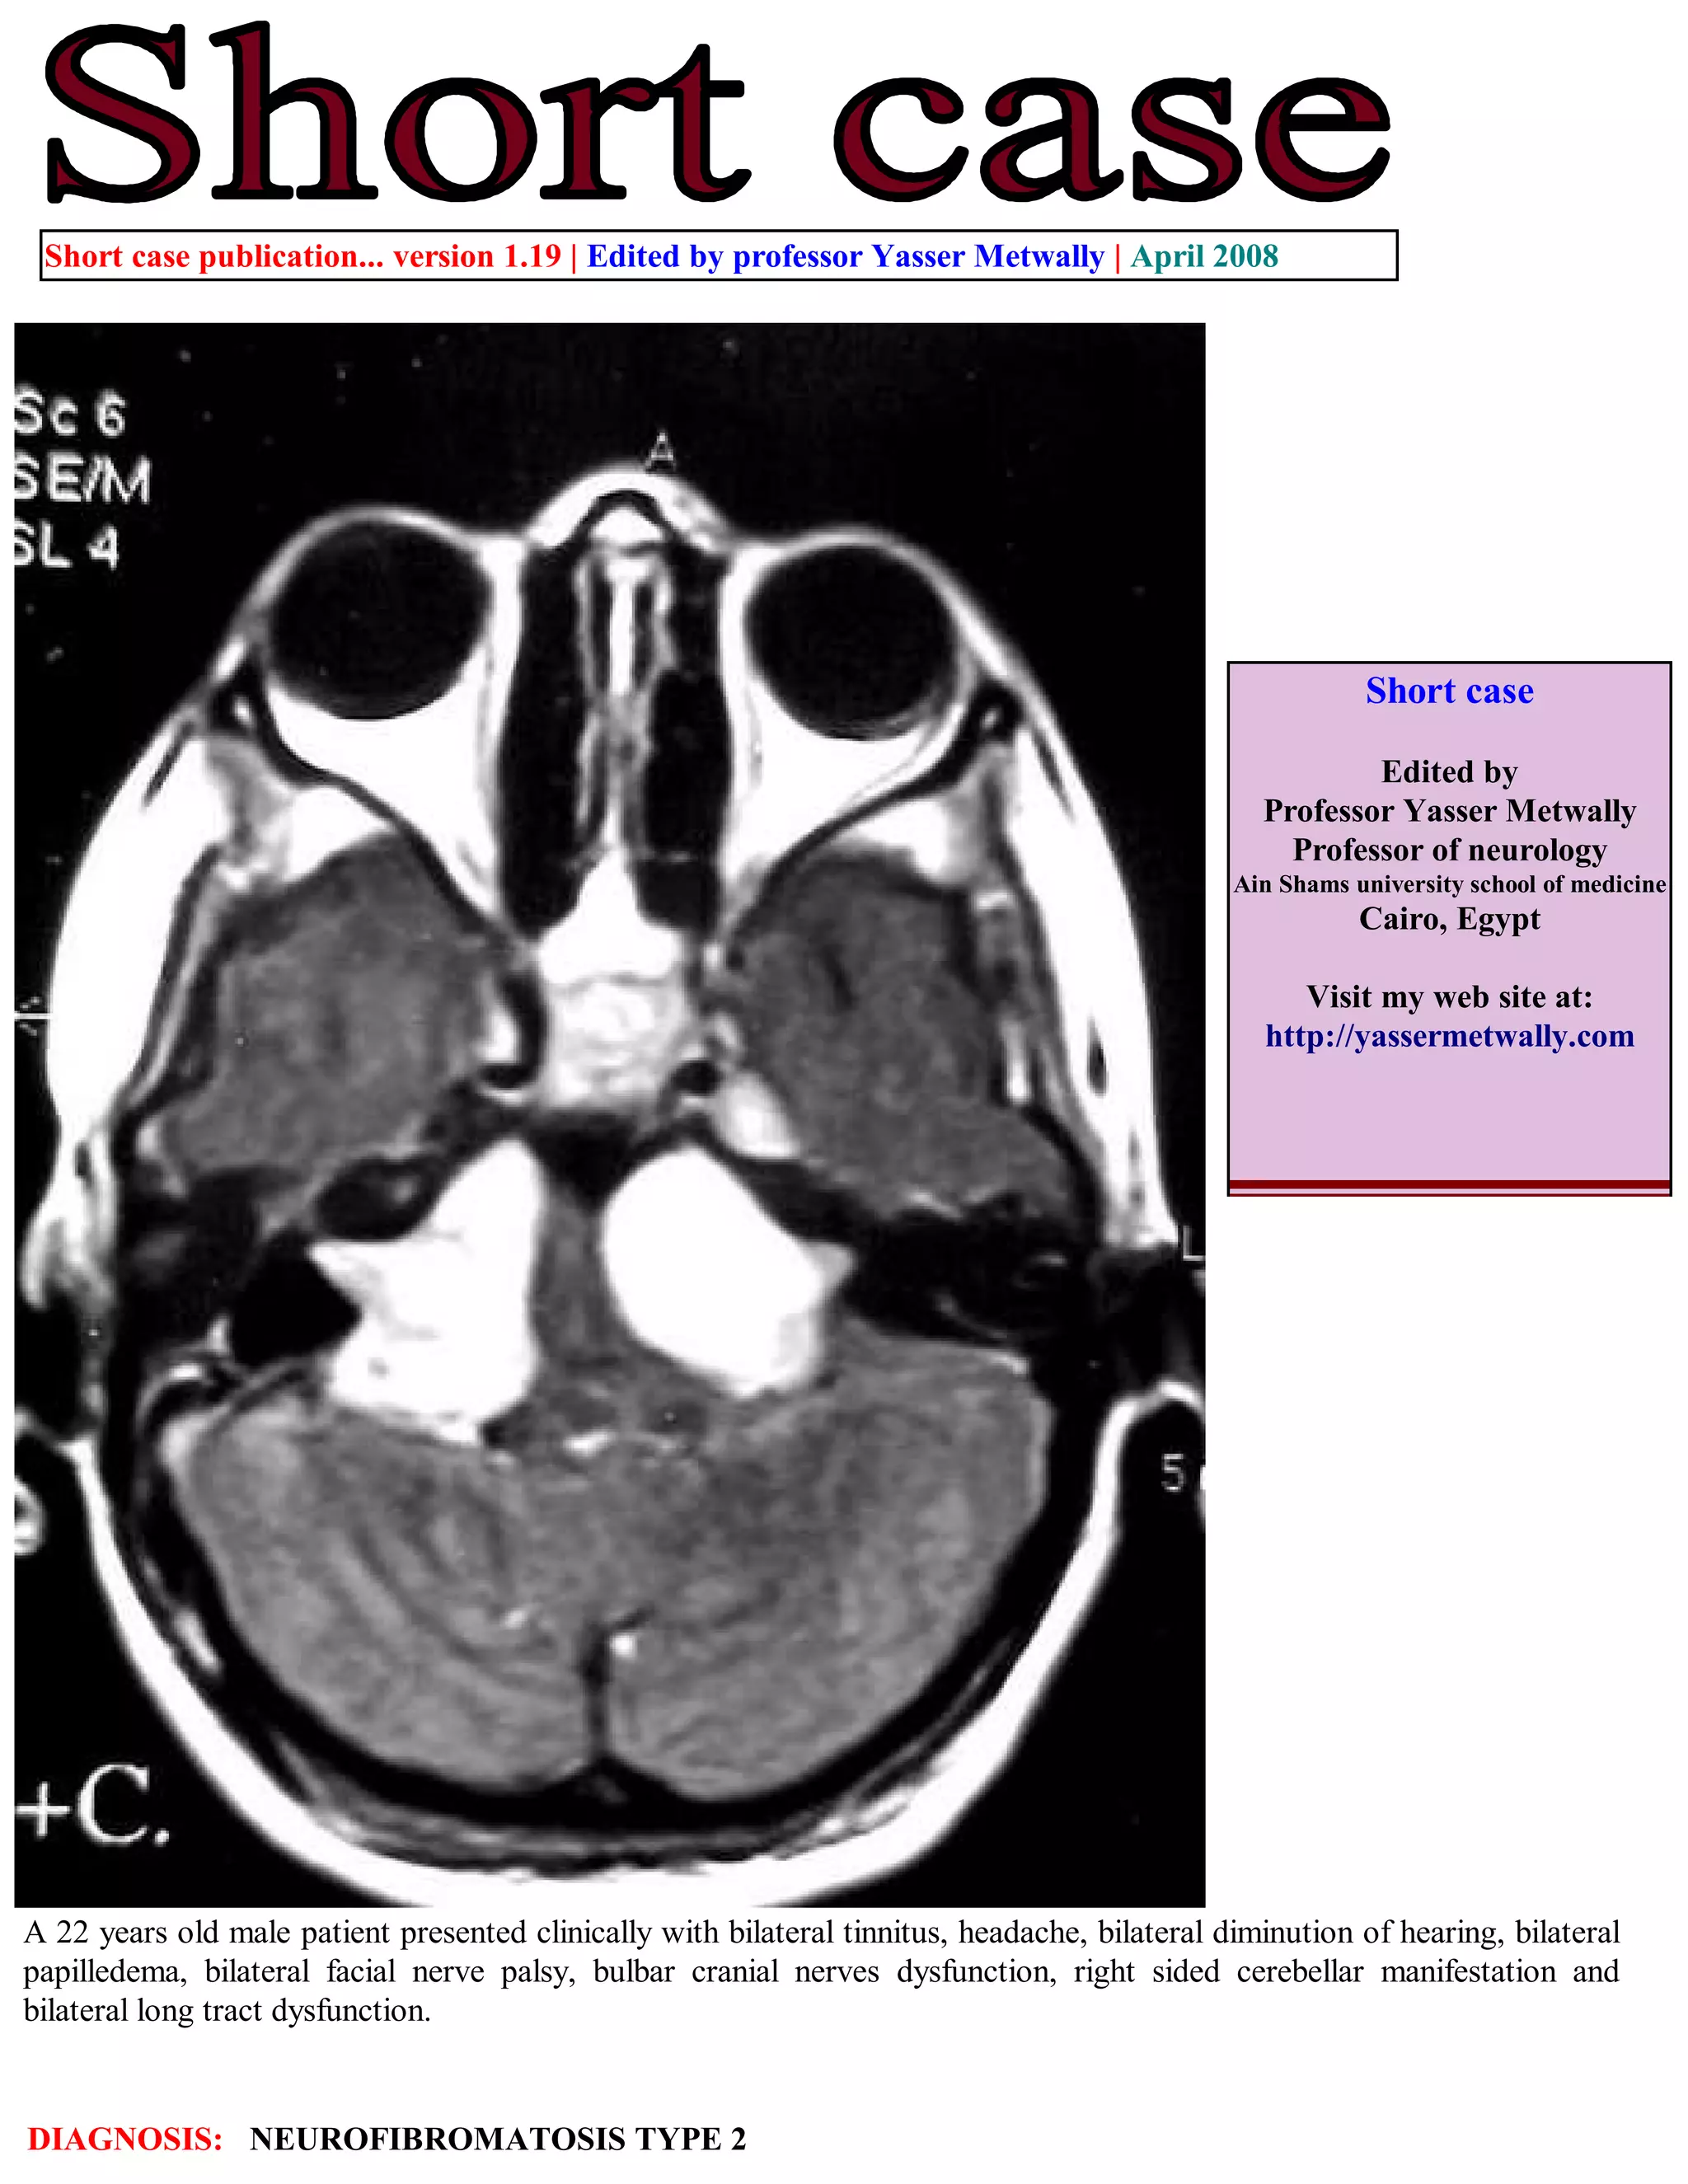

This document is a short case publication from April 2008 edited by Professor Yasser Metwally about a 22-year-old male patient. The patient presented with several neurological symptoms including bilateral tinnitus, headache, hearing loss, eye issues, and mobility issues. The diagnosis was neurofibromatosis type 2 based on MRI scans showing bilateral vestibular schwannomas (tumors on the eighth cranial nerves). The addendum provides information on accessing current and past versions of this case publication online.